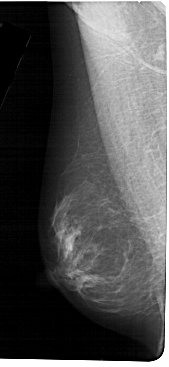

A_1304_1.LEFT_MLO

LEFT_MLO LINES 5491 PIXELS_PER_LINE 2521 BITS_PER_PIXEL 12 RESOLUTION 43.5 NON_OVERLAY